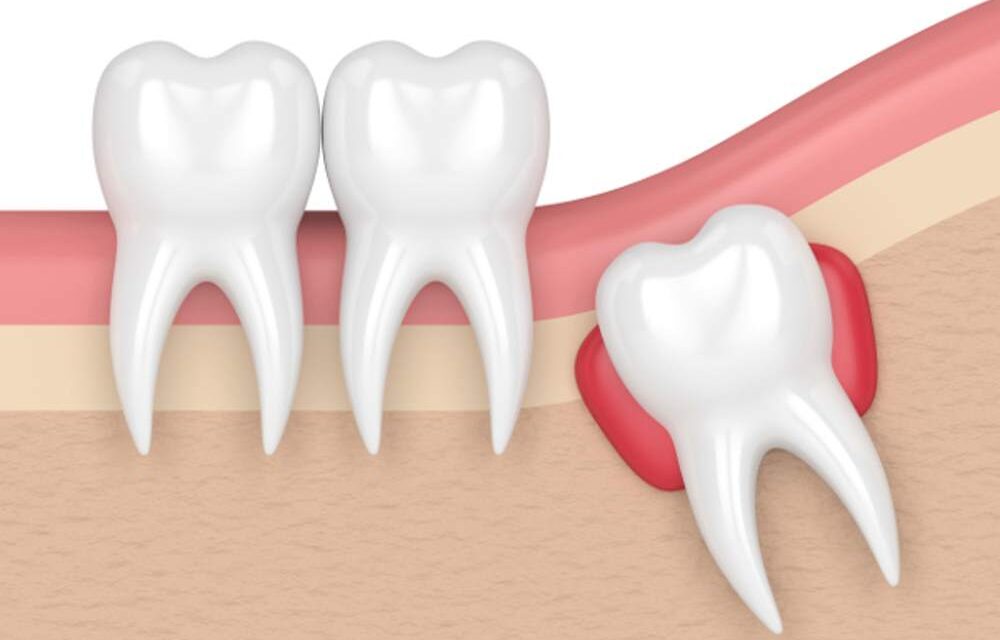

The earlier a cyst is handled, the higher: as talked about, their progress can lead as much as rupture of the alveolar bone the place the tooth is inserted, and likewise transfer the tooth by pushing them collectively, thus modifying the construction of the dental equipment and inflicting different associated issues.

- With a surgical procedure which is carried out underneath native anesthesia. The operation includes the incision of the gum, the potential elimination of the bone protecting the cyst, and the elimination of the epithelium and the contents of the cyst itself.

- If the merchandise is massive, it could be crucial destruction and reconstruction of the identical bone by which the tooth is planted.

- If the tooth is compromised in a sophisticated state, it could be crucial an entire extraction of the tooth.